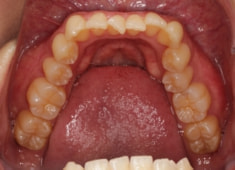

治療開始から24ヶ月後